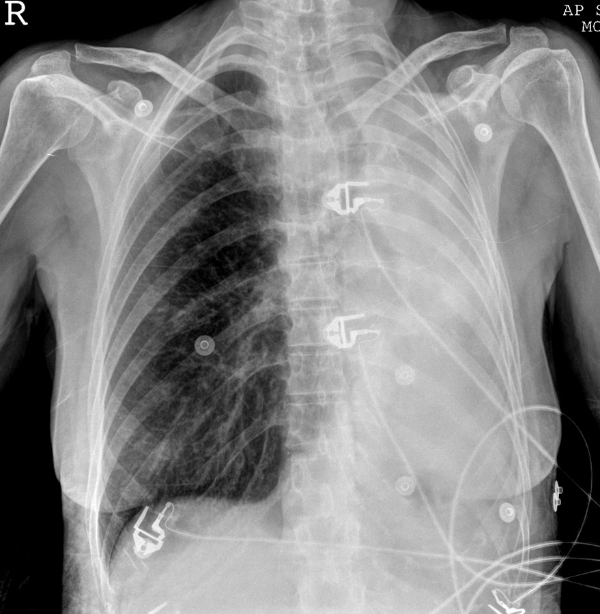

What is shown? Name 2 possible causes.

Left lung collapse/consolidation - considerable mediastinal shift to the left so there must be a considerable loss of lung volume. There is an air bronchogram of at least one of the larger bronchi indicating consolidation.

Pneumonia and obstruction of the left bronchus